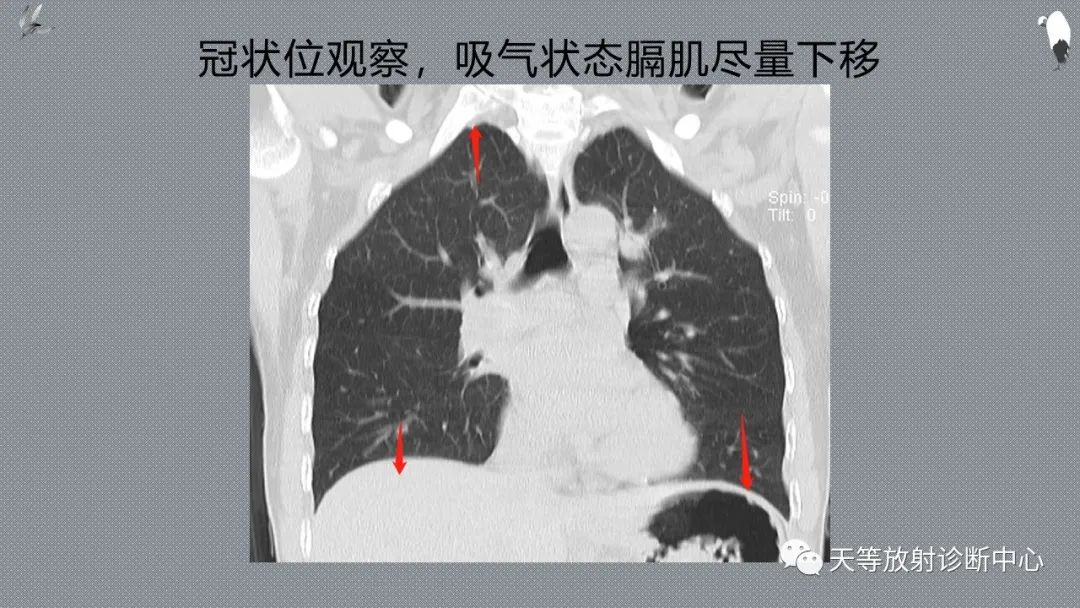

正常吸气及呼气HRCT表现—探索小叶性含气增多影像学

CT可以观察到底是吸气状态还是呼气状态的图像,这有利于对肺内气体量的评价。

充分吸气后进行CT扫描,有利于把肺内正常的含气组织和高密度的肺间质结构进行区分,利用充分显示病灶。